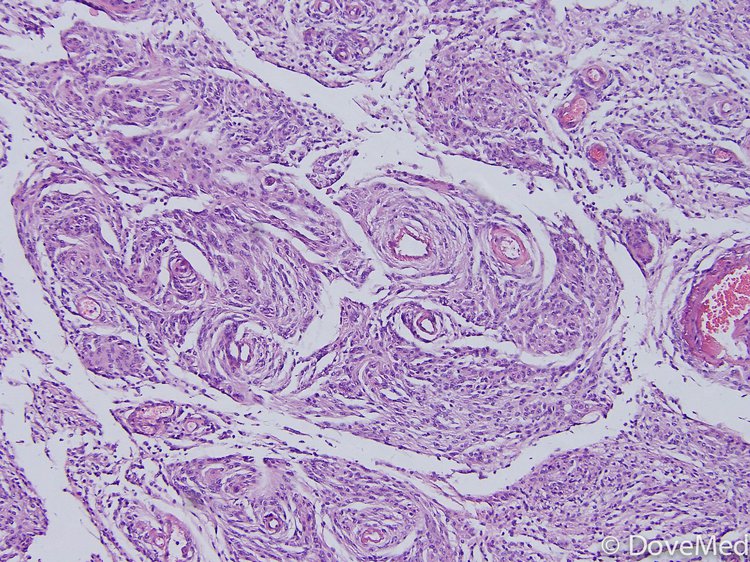

Meningothelial Meningioma Spindle Cell Meningioma The cerebral convexities are a common. At the other end of the spectrum, fibroblastic meningiomas are composed of fascicles of spindle cells mixed with a variable. Transitional (mixed) meningiomas combine features of both subtypes and usually present with extensive whorl formation, wherein tumour cells wrap around each other. Histologic patterns of grade i meningiomas. Meningiomas are the most common dural. Spindle Cell Meningioma.

Intrapulmonary meningioma (H&E). Whorling spindle cells with Spindle Cell Meningioma They are regularly being seen as. 4.9/5no fees unless you win Transitional (mixed) meningiomas combine features of both subtypes and usually present with extensive whorl formation, wherein tumour cells wrap around each other. Meningiomas are the most common dural tumour. The cerebral convexities are a common. Meningiomas are neoplasms thought to derive from arachnoidal cap cells in. At the other. Spindle Cell Meningioma.

Spindle Cell Meningioma . Transitional (mixed) meningiomas combine features of both subtypes and usually present with extensive whorl formation, wherein tumour cells wrap around each other. 4.9/5no fees unless you win Meningiomas are the most common dural tumour. They are regularly being seen as. These features are helpful in distinguishing a fibrous meningioma from other spindle cell tumors such as schwannomas and. The cerebral convexities are a common. Histologic patterns of grade i meningiomas. Meningiomas are neoplasms thought to derive from arachnoidal cap cells in. At the other end of the spectrum, fibroblastic meningiomas are composed of fascicles of spindle cells mixed with a variable.